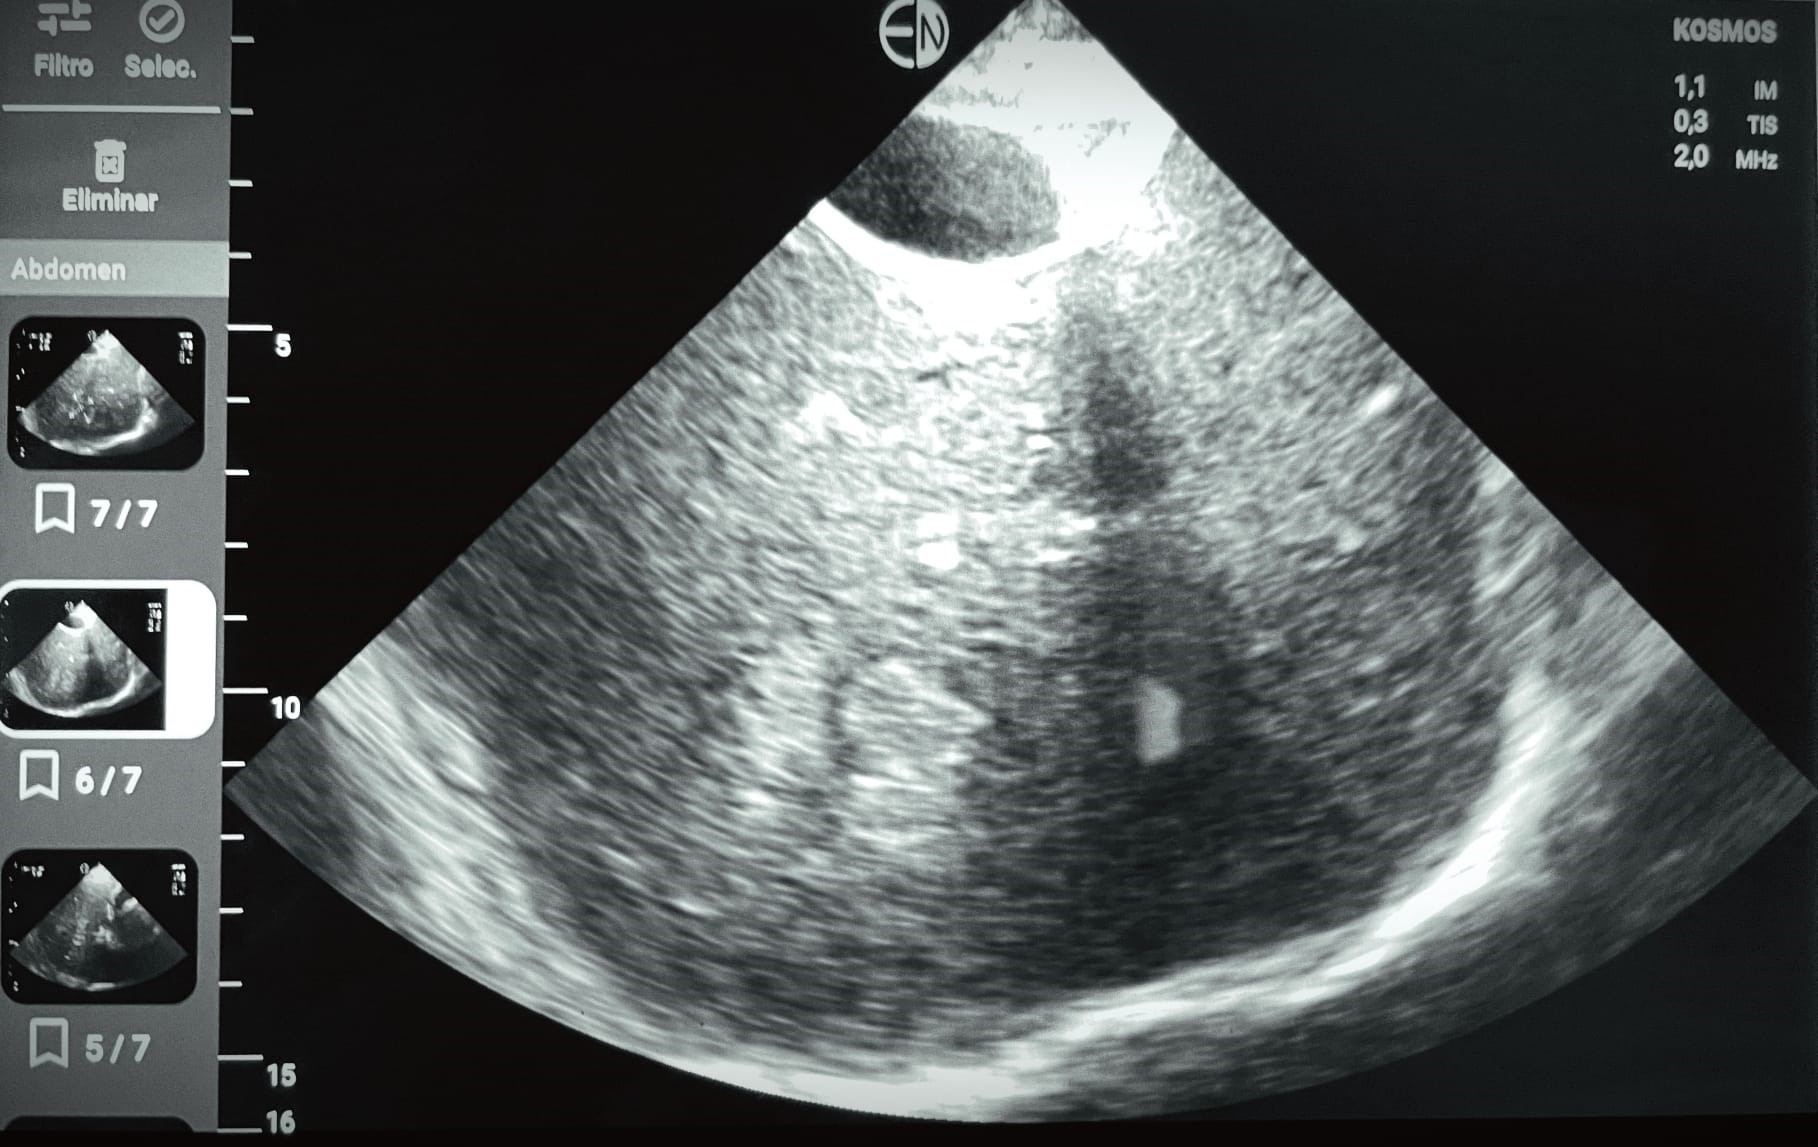

Ecografía POCUS abdomen: se identifican al menos dos imágenes hiperecogénicas en parenquima hepático, con regiones de aspecto algo heterogéneo, la mayor de ellas de 4,9 cm diámetro máx. No líquido libre. Vesícula distendida, sin signos de colecistitis o dilat vía biliar.

Dados los hallazgos exploratorios y ecográficos, así como la imposibilidad de tolerancia oral secundaria a los vómitos, se decide remitir nuevamente a la paciente a Urgencias, donde se termina por realizar TC de abdomen donde se objetiva masa hepática que ocupa la práctica totalidad de los segmentos 2 y 3 del lóbulo hepático izquierdo. Mide aproximadamente 11 x 8 cm. Se observan otras lesiones focales hepáticas (aproximadamente 10), la mayor en segmento 8 de 2,8 cm.